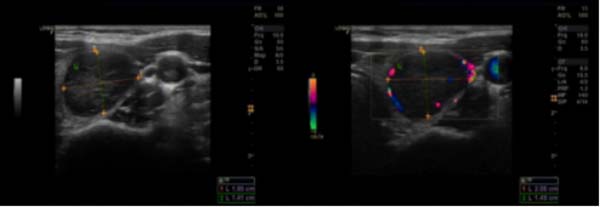

超声所见:甲状腺双叶弥漫性改变,回声不均,内见许多散在低回声区,左叶中部见一个实性低回声区,大小约28×14mm,形态规则,边界清,内部回声不均匀,CDFI:其周边及内部见较丰富血流信号,TI-RADS-3级。

甲状腺透明变梁状肿瘤(hyalinizing trabecular tumor,HTT)是一种向甲状腺滤泡上皮细胞分化的肿瘤。Carney等于1987年报道了11例组织形态学特征不寻常的甲状腺滤泡性肿瘤,并命名为“玻璃样变梁状腺瘤” 。该肿瘤镜下主要以小梁状结构为特征,小梁间有较显著的透明变基底膜样物质沉积,核的特征与甲状腺乳头状癌重叠,并可能与甲状腺髓样癌及副节瘤等肿瘤混淆。HTT临床发病率低,Lee等报道HTT仅占甲状腺结节切除病例的0.2%(10/5111)。该肿瘤女性发病率高于男性,多见于中年女性。临床通常无明显症状,常因体检触诊发现甲状腺结节或影像学检查偶然发现,彩色超声多普勒常表现为甲状腺单发的实性低回声结节,边界清楚,类似于滤泡性肿瘤,结节周边及内部常见血流信号,钙化罕见。